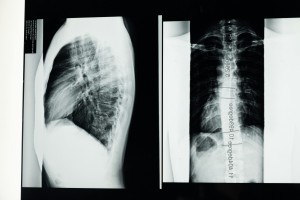

Studies have shown that prolonged poor posture can increase the risk of developing spinal deformities such as kyphosis and lordosis, reduce lung capacity, and cause musculoskeletal imbalances that contribute to long-term pain and discomfort.